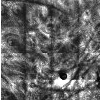

Reflectance Confocal Microscopy for Cutaneous Melanoma Detection

RCM

is a well-established technique that has been shown to

significantly increase the sensitivity and specificity of melanoma

diagnosis when compared with the traditional naked-eye examination. A

CAD system is under development to support the physician during

diagnosis. Collaboration with Città di Lecce Hospital, with Massimo

Federico MD and the group of Giovanni Pellacani MD from Università di

Modena e Reggio.